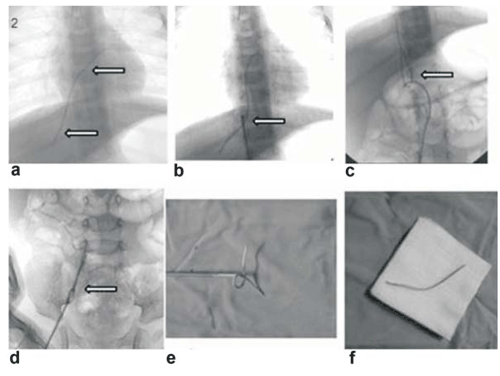

Treinta y nueve cuerpos extraños fueron extraídos sin complicaciones (Figura 2), (Figura 3), (Figura 4) y (Figura 5). Un resto de porth a cath estaba firmemente adherido al trabeculado del ápex del ventrículo derecho, no lográndose su extracción. No se produjeron complicaciones, ni mortalidad vinculadas al procedimiento.

Figura 2: Flechas en a muestran resto de catéter embolizado desde vena suprahepática, aurícula derecha hasta tracto de salida del ventrículo derecho. Captura y extracción por vía vena cava inferior, flechas en b, c y d. En e se muestra el resto de catéter extraído aún fijado al sistema extractor y en f se lo muestra ya liberado.

Figura 5: En a se muestra resto de catéter embolizado en aorta descendente desde arteria umbilical hasta tercio distal de aorta torácica, flechas. En b y c se muestra su captura y extracción vía arteria femoral derecha. En d se lo observa ya extraído y aún fijo al sistema extractor. En e se lo observa liberado.